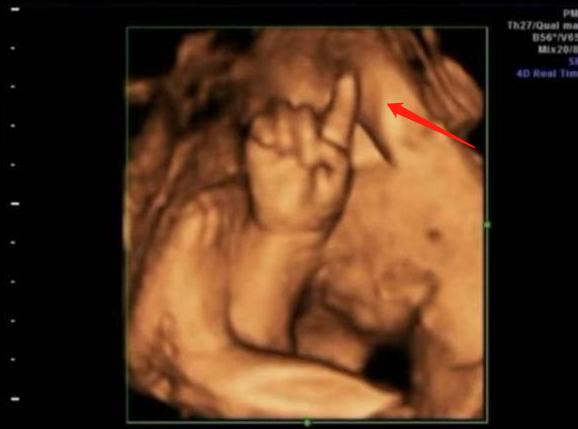

1. “天才”胎儿火了,在子宫里掰手指“算数”,医生:北大清华的料

不怕一万,就怕万一!医生见张女士如此坚持,就给她做了四维检查,结果这一看才发现,胎儿在子宫里“算数”呢!

由于这是她第一次做四维检查,所以胎儿就用手指比划了个“1”。

当张女士第二次来医院做四维检查时,奇迹的情况出现了,这位胎儿竟然又用手指比划了“2”。

张女士十分好奇,觉得胎儿非常有趣,每次做孕检时,都会把胎儿在子宫里的画面拍下来,当她第三次做四维检查时,胎儿的小手也比划了个“3”。

上周,张女士第四次做四维检查,不出意料的是,胎儿的小手比划了个“4”,把所有照片都拼接在一起时,张女士发现胎儿在子宫里“算数”,连起来正好是1234。

对此,医生也觉得十分神奇,笑着说道:

“这孩子看起来是一位数学天才,将来是能念北大清华的料。”

张女士听见这话就乐了,虽然她知道这是医生的玩笑话,但是内心也十分开心。

看到这则消息后,不少网友也都送起了祝福:“真聪明!愿腹中宝宝健健康康、平平安安、白白净净、足月出生!”